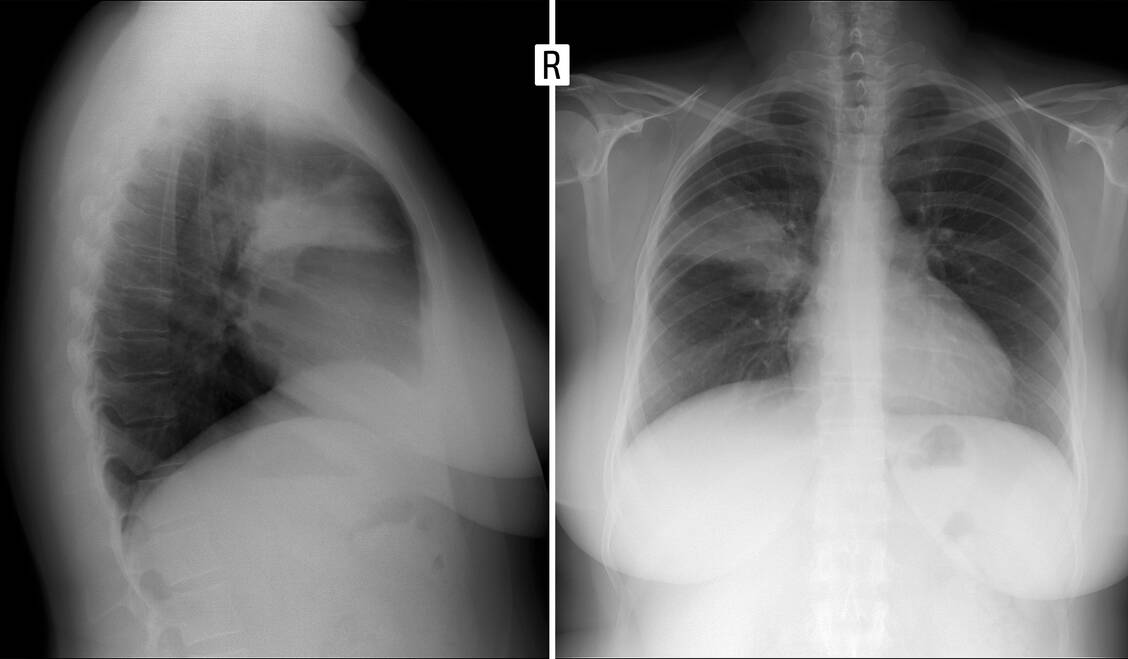

Die Diagnostik bei chronischem Husten ist umfangreicher (Grafik). Die häufigsten Ursachen sind kardiale und neurologische Krankheiten sowie Medikamente, zum Beispiel ACE-Hemmer oder Gliptine. Mit einer Röntgenaufnahme des Thorax in zwei Ebenen sowie einer Lungenfunktionsprüfung kann der Pneumologe in der Regel mehr als die Hälfte der Fälle diagnostizieren.

Röntgenaufnahme der Lunge (Ausschnitt in zwei Ebenen): Es ist eine Pneumonie im Lungenoberlappen rechts zu erkennen (Segment 2). / Foto: Shutterstock/Vanzittoo

Akuter Husten kann auch ein Symptom ernster Lungenerkrankungen sein, zum Beispiel bei einer Lungenentzündung (Pneumonie). Die Symptomkonstellation Husten, gelegentlich mit blutigem Auswurf, sowie mit Fieber, Atemnot, Thoraxschmerz und Zyanose erlaubt die Verdachtsdiagnose. Beweisend ist eine Röntgen-Thorax-Aufnahme. Bei einer Pneumonie sind unbedingt und möglichst frühzeitig Antibiotika erforderlich. Antitussiva können das Schlafen ermöglichen. Ob Expektoranzien den Krankheitsverlauf verbessern, ist umstritten; symptomatisch können sie hilfreich sein.